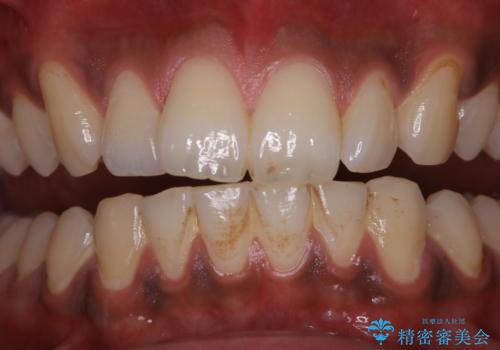

歯についたタバコのヤニをPMTCで綺麗に

- 電子タバコを吸う習慣があり、ステインがついてしまっている見た目が気になるとのことで来院されました。ステインだけではなく、歯石も全体的に付着していたためPMTC60分コースを行いました。